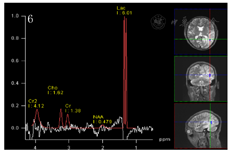

磁共振:磁共振灌注加权成像(PWI):左侧颞枕叶病灶区高灌注。磁共振波谱分析(MRS):左侧颞枕顶叶见大片状长T2信号,脑MRS示将体素置于左侧枕叶病变实性部位,Cho/cr值为1.17,NAA/cr=0.34,cho/NAA的值为3.38, Lac峰出现。(图7)

线粒体脑肌病(1.符合2条核心证据:卒中样发作;影像学表现;2.符合4条支持证据:认知障碍、血乳酸显著增高、磁共振波谱成像显示病灶、≥2次卒中样发作、患者母亲有糖尿病史);

患者中年男性,反复卒中发作,伴有认知下降,外院以"病毒性脑炎"治疗效差,患者外院两次头颅磁共振提示左侧颞枕叶病变,第二次磁共振比第一次病灶面积增大,且磁共振提示病灶为分层样改变,患者发病来无四肢抽搐,根据病史及影像学定位为:大脑皮层、枕叶、左侧锥体束、左侧脊髓丘脑束,定性考虑:卒中?代谢性?炎性?感染?结合患者卒中样发作;影像学表现;认知障碍、血乳酸显著增高、磁共振波谱成像显示病灶、≥2次卒中样发作、患者母亲有糖尿病史、肌电图提示周围神经受累、体重下降、卒中样发作急性期病灶弥散加权成像(DWI)弥散受限,皮质受累尤为明显,呈现类花边征样改变。病灶具有进展性、可逆性、多发性以及呈现"此消彼长"的"游走性"特点[3,4]。